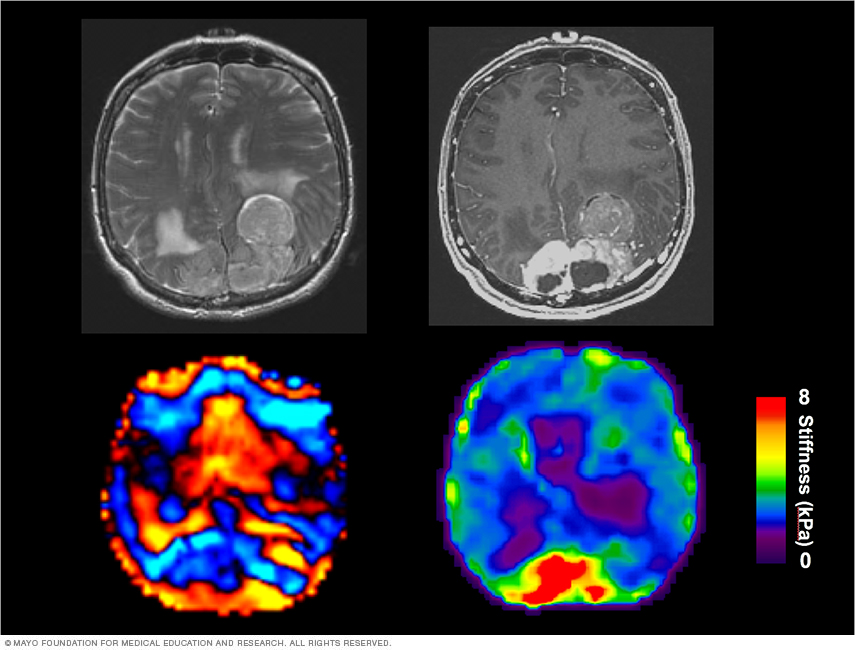

Brain glioblastoma distal from the lateral ventricle Clinical interaction of glioblastoma and subventricular zone

The lateral ventricles in the human brain contain the subventricular zone, an area that maintains production of new neurons in adults. Patients with glioblastoma distal from the lateral ventricle have a better life expectancy than those with tumors contacting the lateral ventricle.